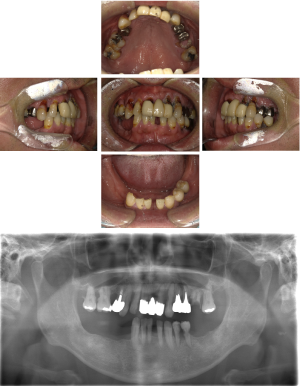

30代 女性 奥歯 インプラント

| 年代・性別 | 30代・女性 |

| 治療回数 | 10回(術前治療・検査除く) |

| 治療期間 | 約1年 |

| 料金 | ¥410,300(税込)※別途検査料 |

失った歯を補うために、インプラント治療は優れた治療方法です。 しかし、全ての人にインプラント治療が優れている治療ではありません。 |

| 副作用 | 術後に腫れ・痛みが出る可能性がある。 |